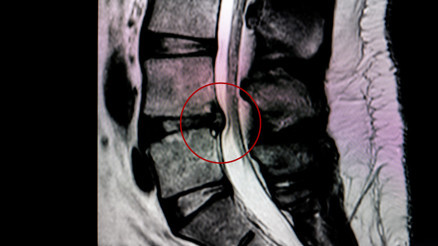

#Trafik KavgasıBeyin ve Sinir Cerrahisi Uzmanı Prof. Dr. Selçuk Göçmen, bel fıtığının modern tıpla artık yönetilebilir bir sorun haline geldiğini söyledi. Gün boyu oturanlardan ağır iş yapanlara kadar herkesi etkileyen bu rahatsızlıkta, doğru duruş, hareket ve yaşam tarzı değişiklikleri büyük fark yaratıyor. Prof. Dr. Göçmen, bel fıtığı riskini azaltacak 9 hayati önlem ve tedavi sürecinde dikkat edilmesi gereken noktaları vurguladı. Peki, hastalar nelere dikkat etmeli?